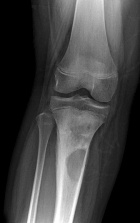

13 yo male with several months of right shin pain. No history of trauma. He describes the pain as sharp and stabbing and is now secondarily unable to bear weight. He complains of decreased appetite and pain at night.

PE: RLE: Palpable, tender mass with associated erythema and edema at proximal, medial calf. Pain with flexion greater than 90 degrees at the knee. Achieves full extension. NVI w/o LAN

WBC11.3, sed rate of 26, and CRP of 10.4